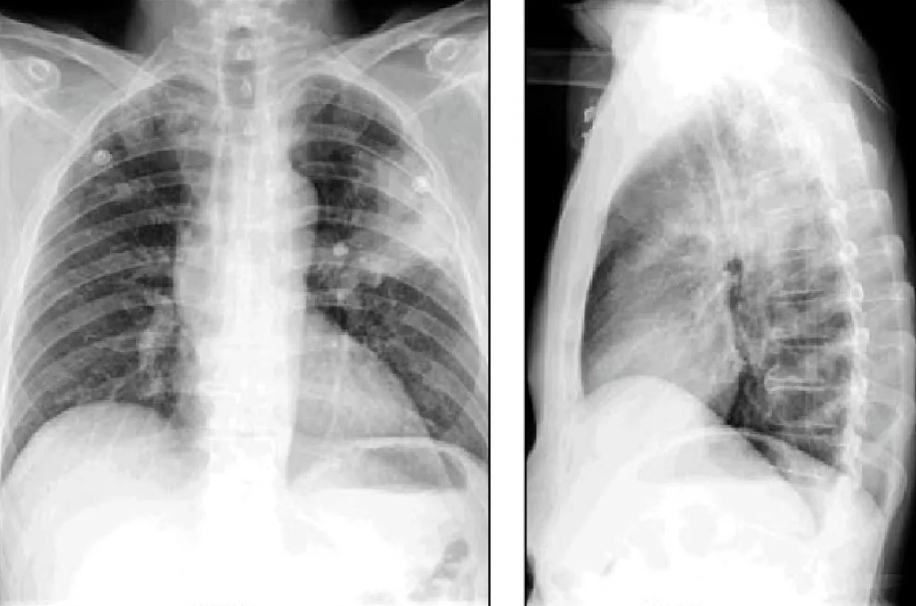

en la rx de torax, la neumonia se observa _

A

radiopaca